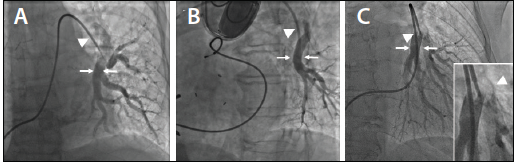

Figure 2. Selective pulmonary angiography is used to estimate vessel size. The size of the vessel at the implant location (arrows) is approximately 9 to 10 mm in diameter, estimated by comparing the size of the vessel to the adjacent tip of the balloon wedge catheter (arrowhead, 2.3 mm, 7 F) (A). The size of the vessel at the implant location (arrows) is approximately 7 to 8 mm in diameter, estimated by comparing the size of the vessel to the adjacent tip of the balloon wedge catheter (arrowhead, 2.3 mm, 7 F) (B). The size of the vessel is approximately 9 to 10 mm in diameter, estimated by comparing the size of the vessel to the inflated balloon of the balloon wedge catheter (arrowhead, 10 mm) (C). The inset shows a magnified view of the inflated balloon wedge catheter (arrowhead) (C).

Femoral access is achieved using standard techniques with the initial sheath upsized to a standard 12-F sheath. A 7-F Arrow balloon wedge catheter (Teleflex) is favored over the traditional 7-F Swan-Ganz catheter (Edwards Lifesciences), as it is easier to manipulate from the femoral approach into the left PA and allows improved imaging for pulmonary angiography, given the balloon wedge catheter’s 0.035-inch lumen compared to the 0.025-inch lumen of the Swan-Ganz catheter. Accurate measurement of cardiac filling pressures and cardiac output allows assessment of cardiovascular status and provides a prescription for adjustment of HF medications. Selective pulmonary angiography is performed using an automated injection system or via hand injection to define an appropriate implant location.

The ideal location for the implant is a left-sided, posteriorly directed PA branch measuring 7 to 11 mm in diameter with an appropriate distal vessel length to allow a stable and safe position for the 0.018-inch guidewire (Figure 2). Left anterior oblique or lateral projection imaging can confirm that the chosen branch travels in a posterior direction. Vessel size can be estimated by visual assessment using an adjacent catheter or inflated balloon (Figure 2). Quantitative vessel angiography is not required. Multiple selective angiograms may be required to identify an optimal implant site. In the absence of an appropriately sized left-sided PA branch, the sensor can be implanted into a right-sided PA branch. Fluoroscopic landmarks such as ribs, coronary calcium, coronary stents, and pacer/implantable defibrillator wires can be used to establish the desired implant location (Figure 3). Additional supplies that may be required for the implantation procedure include an angled catheter (JR4 or KMP) or 0.035-inch angled standard Glidewire (Terumo Interventional Systems), which can be used to engage the left PA when catheter rotation fails to enter the left PA.